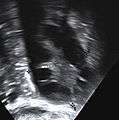

Transvaginal ultrasound scan of polycystic ovary

- Gynecologic ultrasonography, specifically looking for small ovarian follicles. These are believed to be the result of disturbed ovarian function with failed ovulation, reflected by the infrequent or absent menstruation that is typical of the condition. In a normal menstrual cycle, one egg is released from a dominant follicle – in essence, a cyst that bursts to release the egg. After ovulation, the follicle remnant is transformed into a progesterone-producing corpus luteum, which shrinks and disappears after approximately 12–14 days. In PCOS, there is a so-called "follicular arrest"; i.e., several follicles develop to a size of 5–7 mm, but not further. No single follicle reaches the preovulatory size (16 mm or more). According to the Rotterdam criteria, 12 or more small follicles should be seen in an ovary on ultrasound examination.[37] More recent research suggests that there should be at least 25 follicles in an ovary to designate it as having polycystic ovarian morphology (PCOM) in women aged 18–35 years.[43] The follicles may be oriented in the periphery, giving the appearance of a 'string of pearls'.[44] If a high resolution transvaginal ultrasonography machine is not available, an ovarian volume of at least 10 ml is regarded as an acceptable definition of having polycystic ovarian morphology instead of follicle count.[43]

The syndrome acquired its most widely used name due to the common sign on ultrasound examination of multiple (poly) ovarian cysts. These "cysts" are actually immature follicles not cysts. The follicles have developed from primordial follicles, but the development has stopped ("arrested") at an early antral stage due to the disturbed ovarian function. The follicles may be oriented along the ovarian periphery, appearing as a 'string of pearls' on ultrasound examination.